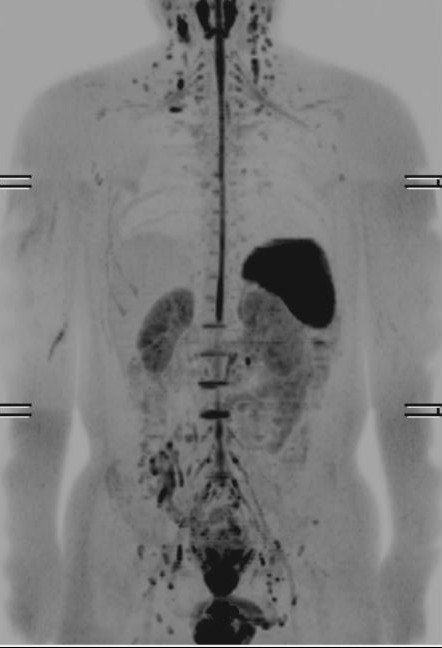

拡散強調画像

MRI撮像法の1つで、水分子の拡散運動を画像として反映させています。腫瘍・梗塞・炎症などの病変はこの拡散運動が小さくなるということが分かっており、この状態を画像化することによって、これらの病変を検出することができます。従来、当センターでは全身撮影を行う場合、約40分~50分の時間を要していました。しかし、新しく導入したMRI装置で全身撮影を行う場合、約20分の撮影が可能になりました。